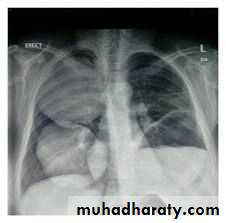

Severe dyspnea with shock